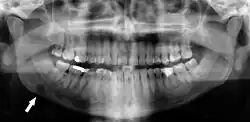

Panoramic radiographs have the capability to demonstrate a portion of the neck and display atheromas (calcifications in the carotid artery) which are an indication of both local and generalized (systemic) atherosclerosis. Atherosclerosis of the coronary arteries leading to myocardial infarction (heart attack), and atherosclerosis of the carotid artery leading to stroke are the number one and number three most common causes of death in the United States.[6]

There is interest to look at panoramic radiographs as a screening tool, however further data is needed with regards if it is able to make a meaningful difference in outcomes.[7]

Additional research projects have further determined the prevalence rate of these atheromas in the general population (3–5%)[8][9] and among high-risk groups (over 25% in: recent stroke victims,[10] individuals with obstructive sleep apnea syndrome,[11][12][13] postmenopausal women,[14] type 2 diabetics,[15][13][16] individuals with dilated cardiomyopathy,[17][13] and among individuals who have received radiotherapy directed at the neck,[18][19]). These findings have been corroborated by other several other researchers.[20][21][22][23][13]

Atherosclerosis is attributed to risk factors that include cigarette smoking, hyperlipidemia, obesity, diabetes mellitus, and hypertension (high blood pressure). These factors, however, do not fully account for the risk of disease. Atherosclerosis has been conceptualized as a chronic inflammatory response to endothelial cell injury[24] and dysfunction possibly arising from chronic dental infection. In 2010, using the previously validated Mattila panoramic radiographic index to quantify the totality of dental infection (i.e., periapical and furcal lesions, pericoronitis sites, carious tooth roots, teeth with pulpal caries, and vertical bony defects), Friedlander's group determined that individuals with carotid artery atheromas on their panoramic radiographs had significantly greater amounts of dental infection/inflammation than atherogenic risk-matched controls devoid of radiographic atheromas.[25][26] While the Mattila index had been previously used to relate the extent of dental infection to coronary artery disease, this research is the first to link the full range of dental disease that it measures to panoramic radiographs evidencing calcified carotid artery atherosclerosis.